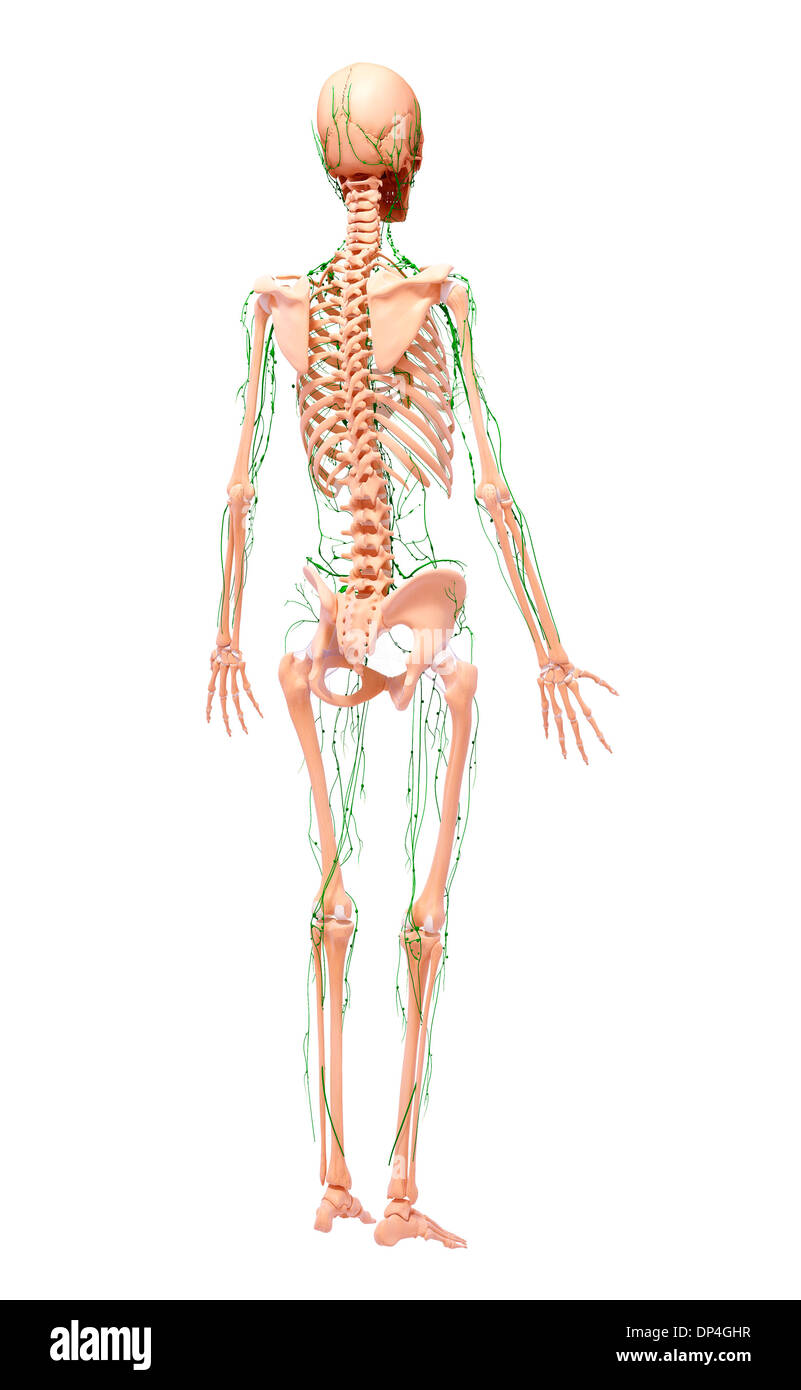

Système lymphatique humain, artwork Banque D'Imageshttps://www.alamyimages.fr/image-license-details/?v=1https://www.alamyimages.fr/systeme-lymphatique-humain-artwork-image65254387.html

Système lymphatique humain, artwork Banque D'Imageshttps://www.alamyimages.fr/image-license-details/?v=1https://www.alamyimages.fr/systeme-lymphatique-humain-artwork-image65254387.htmlRFDP4GHR–Système lymphatique humain, artwork